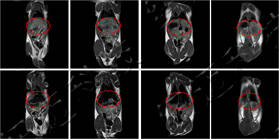

儀器使用小動物核磁共振成像系統,圖像為T1加權像橫斷面、冠狀面,采樣參數如下:FOV=100mm×100mm, TR=400ms, TE=19ms, 層厚3.5mm, 層間距1mm, 累加次數16, K空間大小192×256。成像結果顯示,注射造影劑后,大鼠心臟與肝臟變亮,且隨代謝時間延長逐漸變暗。

大鼠造影前后MRI冠狀面